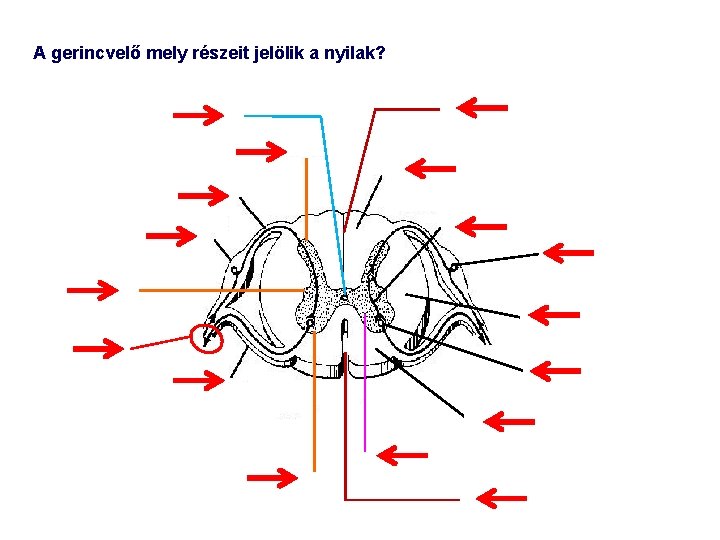

A gerincvelő mely részeit jelölik a nyilak? Hátulsó középbarázda Központi csatorna Hátsó szarv (érző működés) Gerincvelői ideg hátulsó gyökere (érző működés) Fehérállomány; hátulsó köteg Interneuron Csigolya közti dúc Pszeudo-unipoláris érző neuron (sejttestje) Oldalsó szarv (vegetatív működés) Fehérállomány; oldalsó köteg Gerincvelői ideg Mozgató neuron Gerincvelői ideg elülső gyökere (mozgató, végrehajtó működés) Fehérállomány; elülső köteg Szürkeállomány Elülső szarv (mozgató, végrehajtó működés) Elülső középbarázda